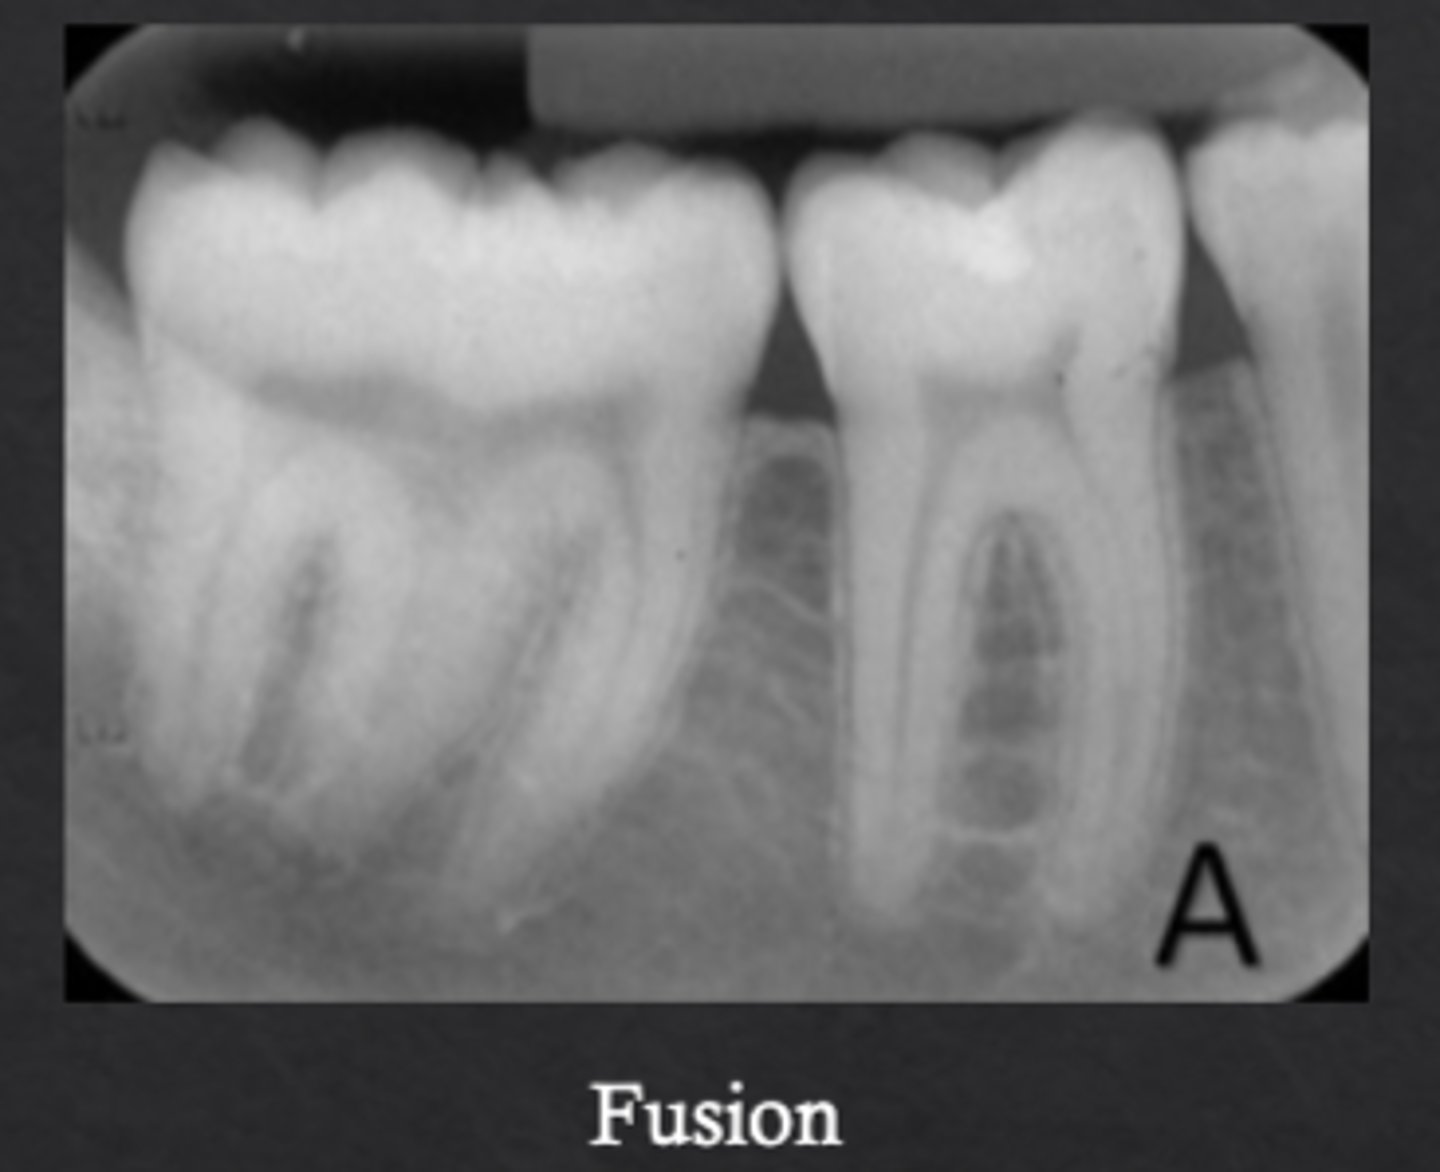

What is fusion?

Two tooth buds fuse to form one tooth

How many teeth are present in fusion cases?

One fewer than normal

What is gemination?

One tooth bud attempts to divide into two crowns

How many teeth are present in gemination cases?

Normal number of teeth